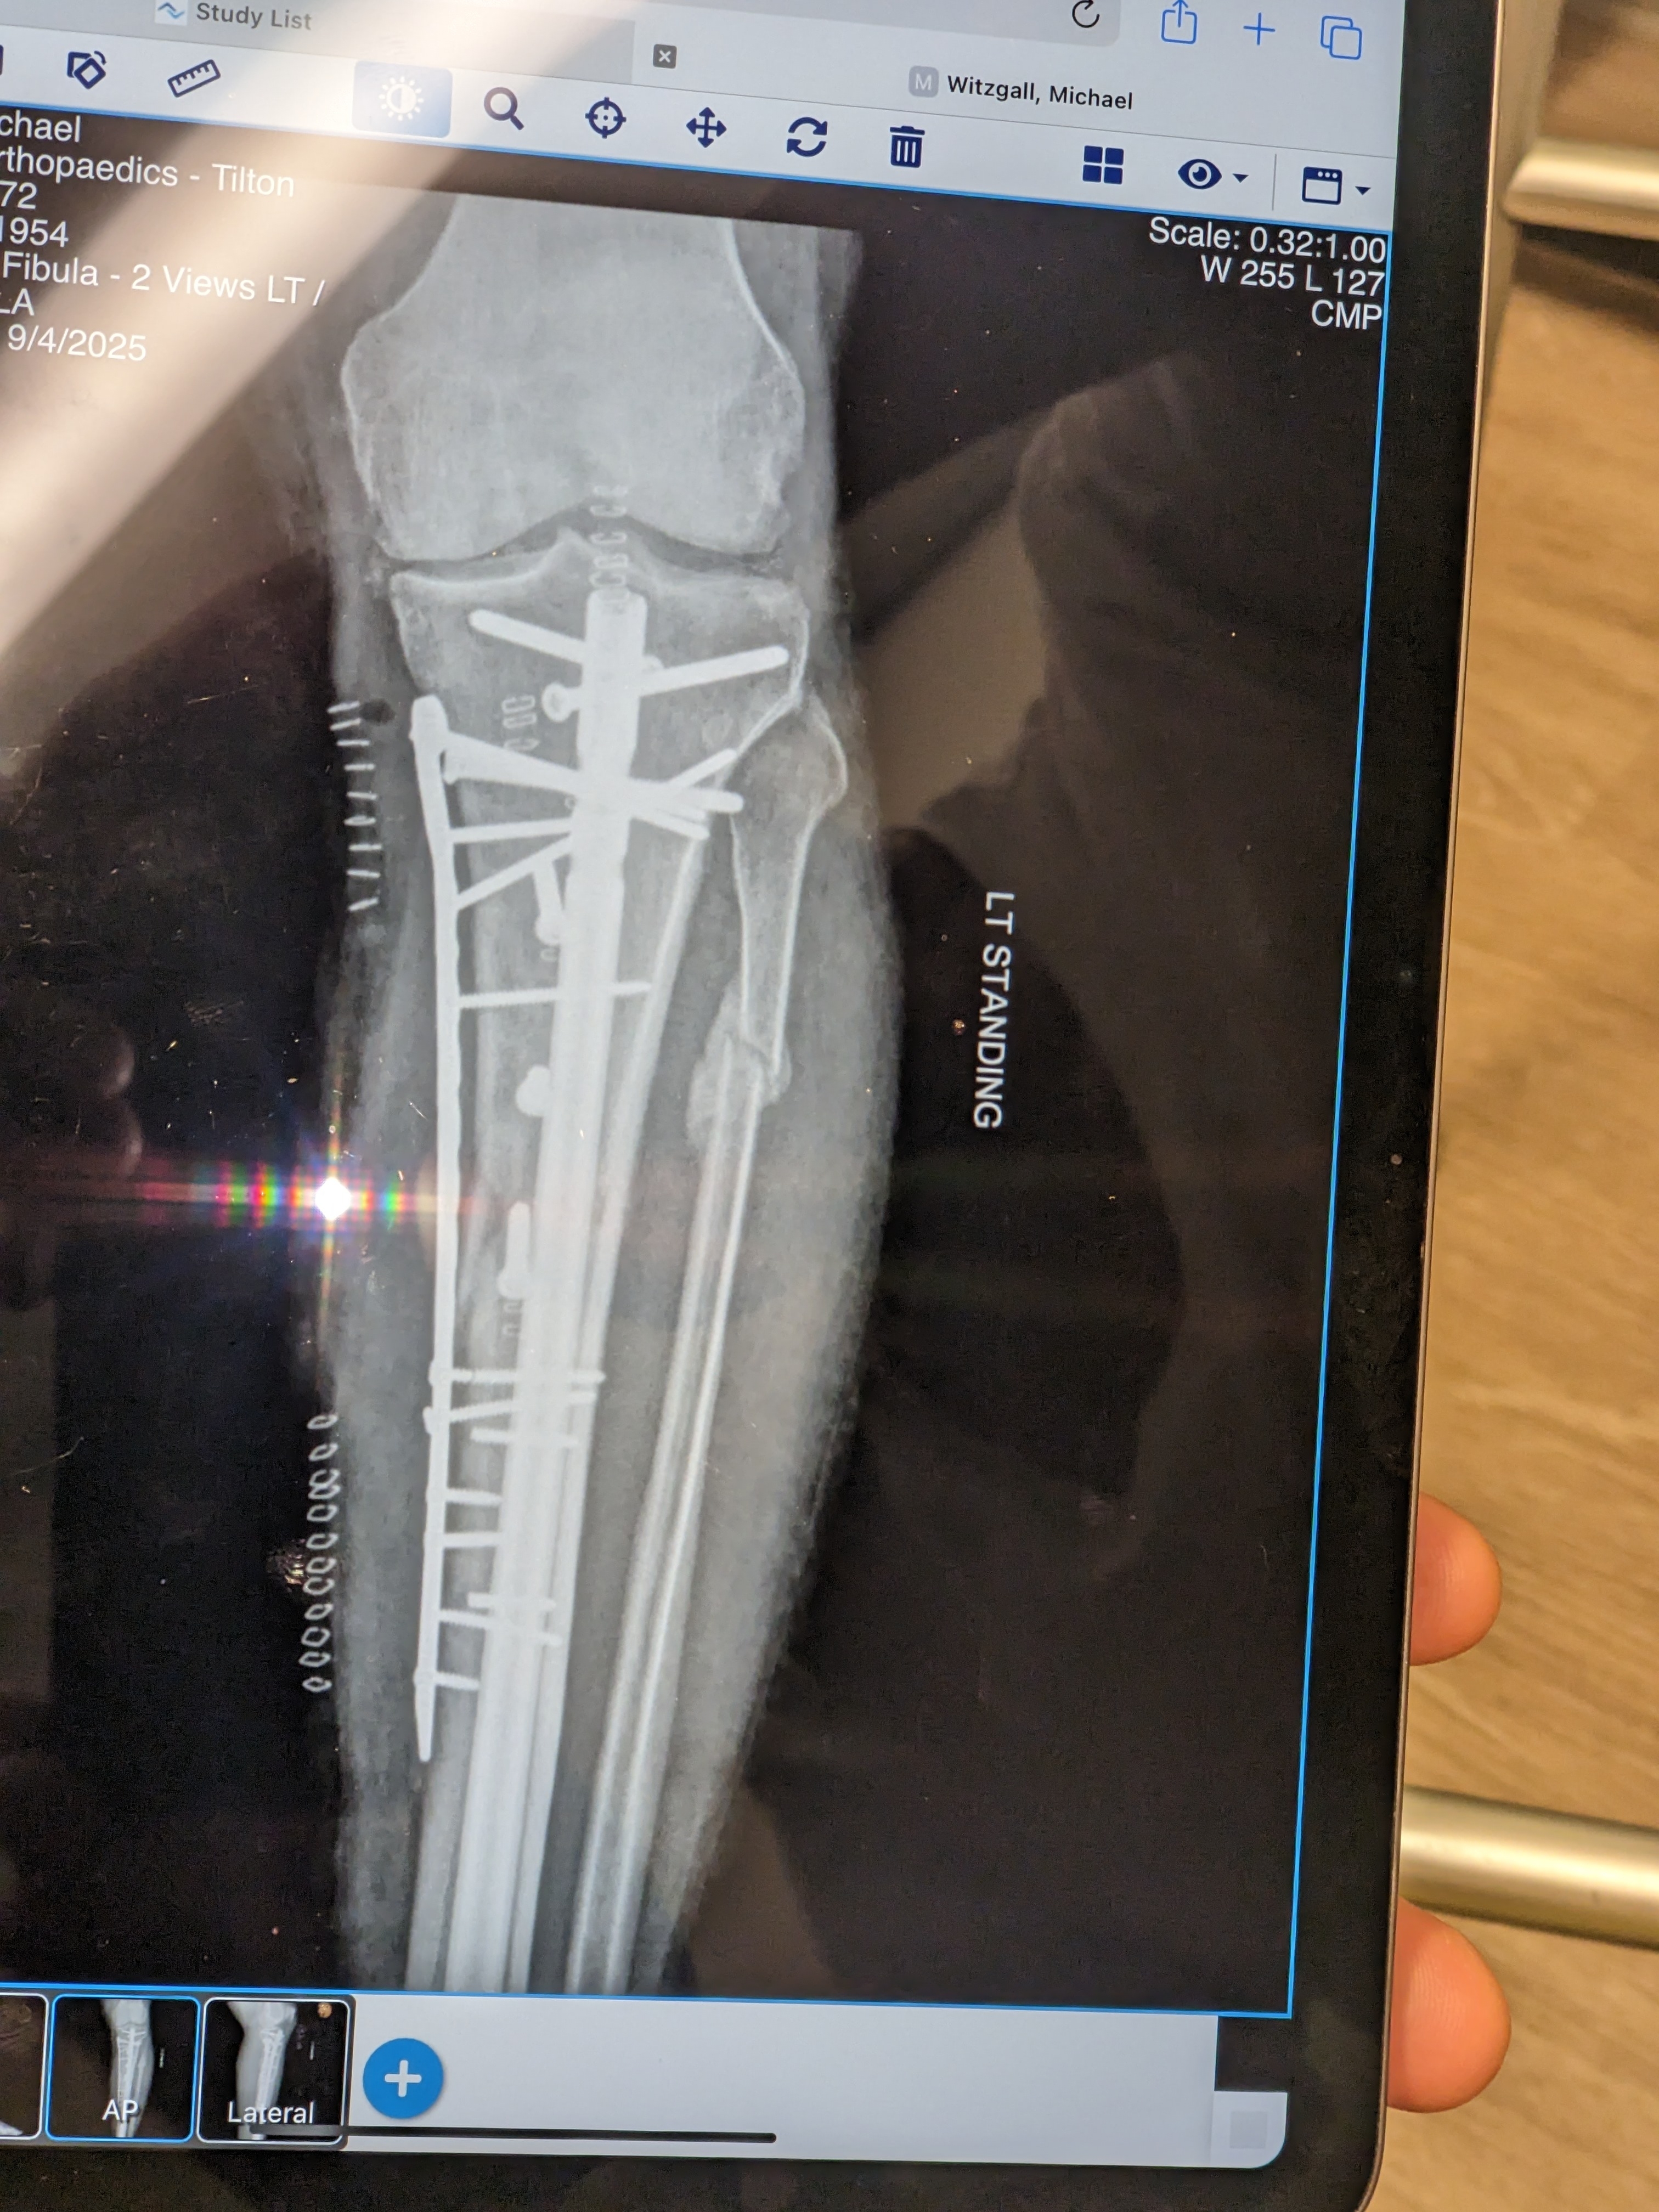

I got my original hardware back that was removed and replaced with the Superduty stuff. I wonder if these items can be resold to third world regions in need of medical implants?

New hardware is providing more stability. Now only hope the crunched Tibia begins to mend.